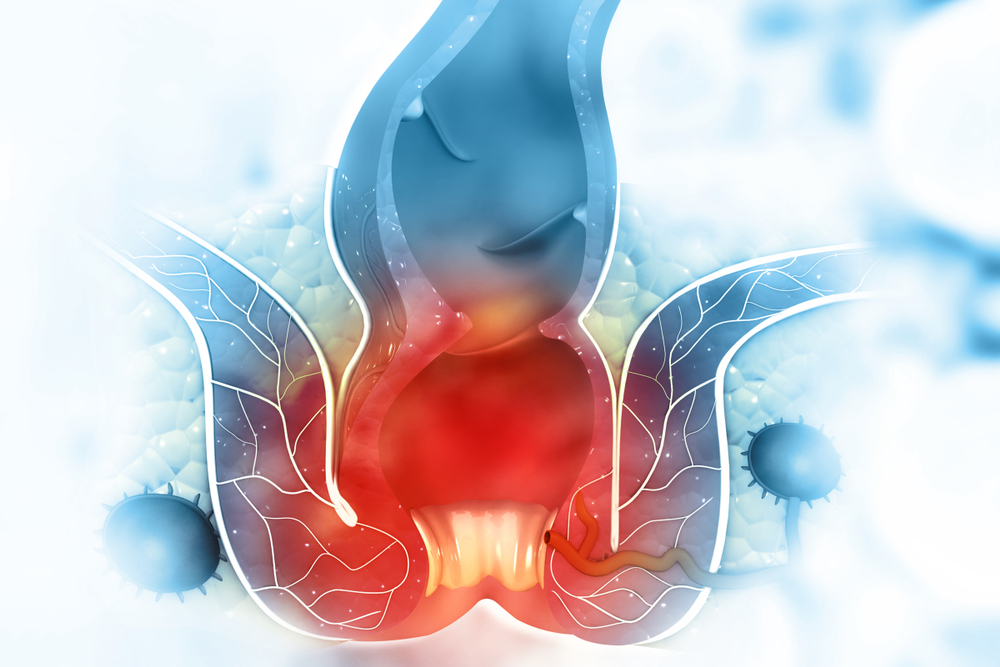

بواسیر چیست؟

بواسیر، در واقع التهاب و تورم وریدهای ناحیه مقعد و انتهای راستروده است که میتواند داخلی (درون مقعد) یا خارجی (در اطراف دهانه مقعد) باشد. این رگها به طور طبیعی در بدن وجود دارند، اما هنگامی که فشار داخل شکم یا راستروده افزایش مییابد، دیواره آنها گشاد و ضعیف شده و به صورت تودههایی متورم ظاهر میشوند.

نقش یبوست در ایجاد بواسیر

در افرادی که به یبوست مبتلا هستند، دفع مدفوع معمولاً با فشار و زور زدن شدید همراه است. این رفتار باعث افزایش قابل توجه فشار در ناحیه لگن و اطراف رگهای مقعدی میشود. در نتیجه، این رگها به مرور زمان کشیده شده، خاصیت ارتجاعی خود را از دست میدهند و متورم میشوند.

همچنین، خشکی مدفوع که یکی از علائم اصلی یبوست است، خود یک عامل مکانیکی تحریککننده است که میتواند با آسیب به بافتهای ناحیه مقعد، زمینه را برای خونریزی و التهاب هموار کند. به همین دلیل است که بسیاری از مبتلایان به بواسیر، ابتدا سابقهای از یبوست درماننشده یا عود کننده دارند.